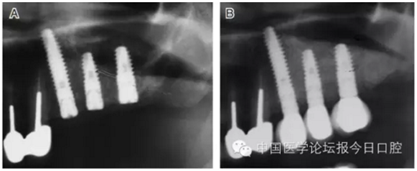

病例5 多顆種植體(圖7)

圖7

病例6 應(yīng)用骨替代材料遠(yuǎn)期觀察(圖8)

圖8